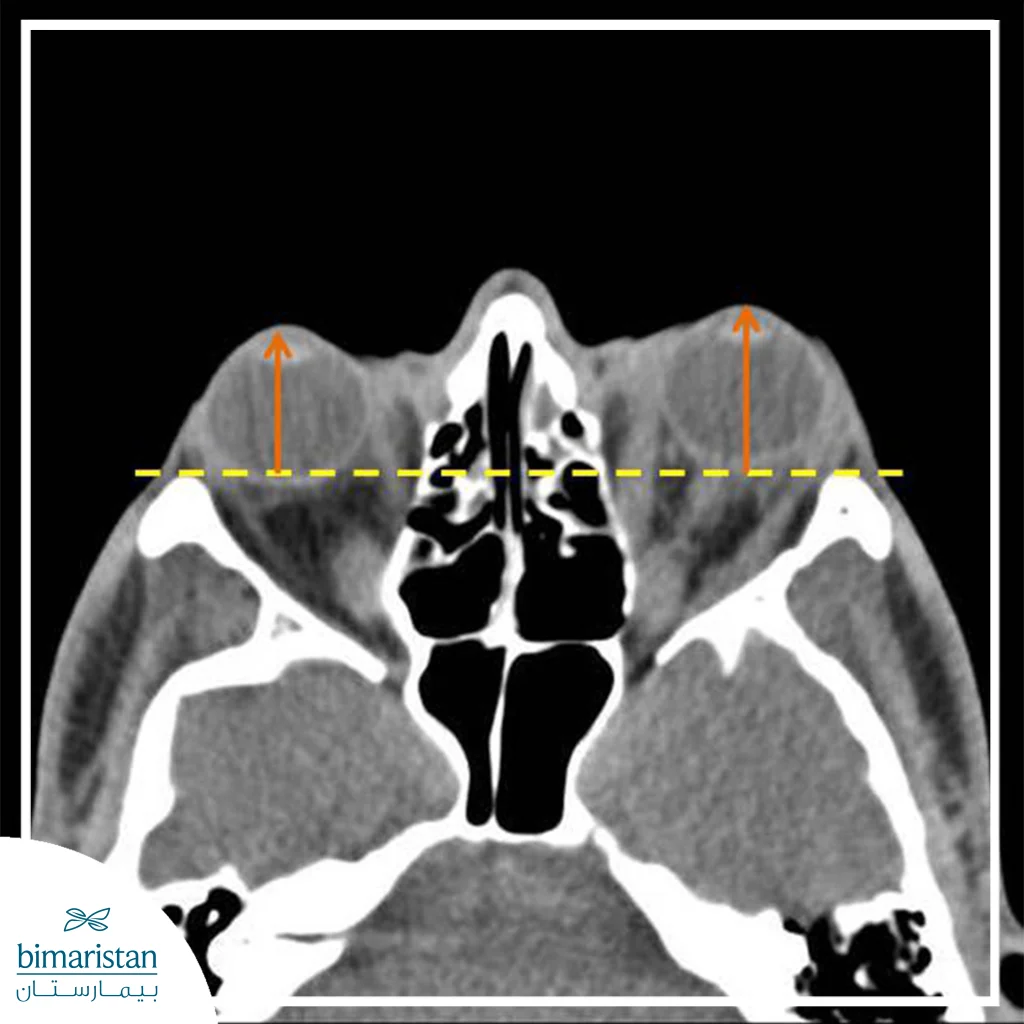

Orbital decompression is a surgical procedure that aims to reduce the pressure inside the eye socket by increasing the space available for its contents. This is achieved by removing part of the bony orbital walls, removing part of the orbital fat, or a combination of both, depending on the nature and severity of the condition.

This procedure helps to allow the enlarged tissue to expand into the neighboring spaces, reducing pressure on the eye and optic nerve and improving the intraorbital position of the eye. The exact type of surgical intervention is determined after a thorough clinical and radiographic evaluation.

In this type, specific parts of the bony orbital walls, such as the medial or inferior wall, are removed, allowing tissue to move into neighboring sinuses. This technique is often used in moderate to severe cases.

Before making a surgical decision, the patient undergoes a comprehensive evaluation that includes an eye examination, visual acuity assessment, eye movement, and radiographic imaging such as CT or MRI to determine the cause and severity of the pressure. The patient’s general condition is also stabilized, especially in cases associated with thyroid disorders.